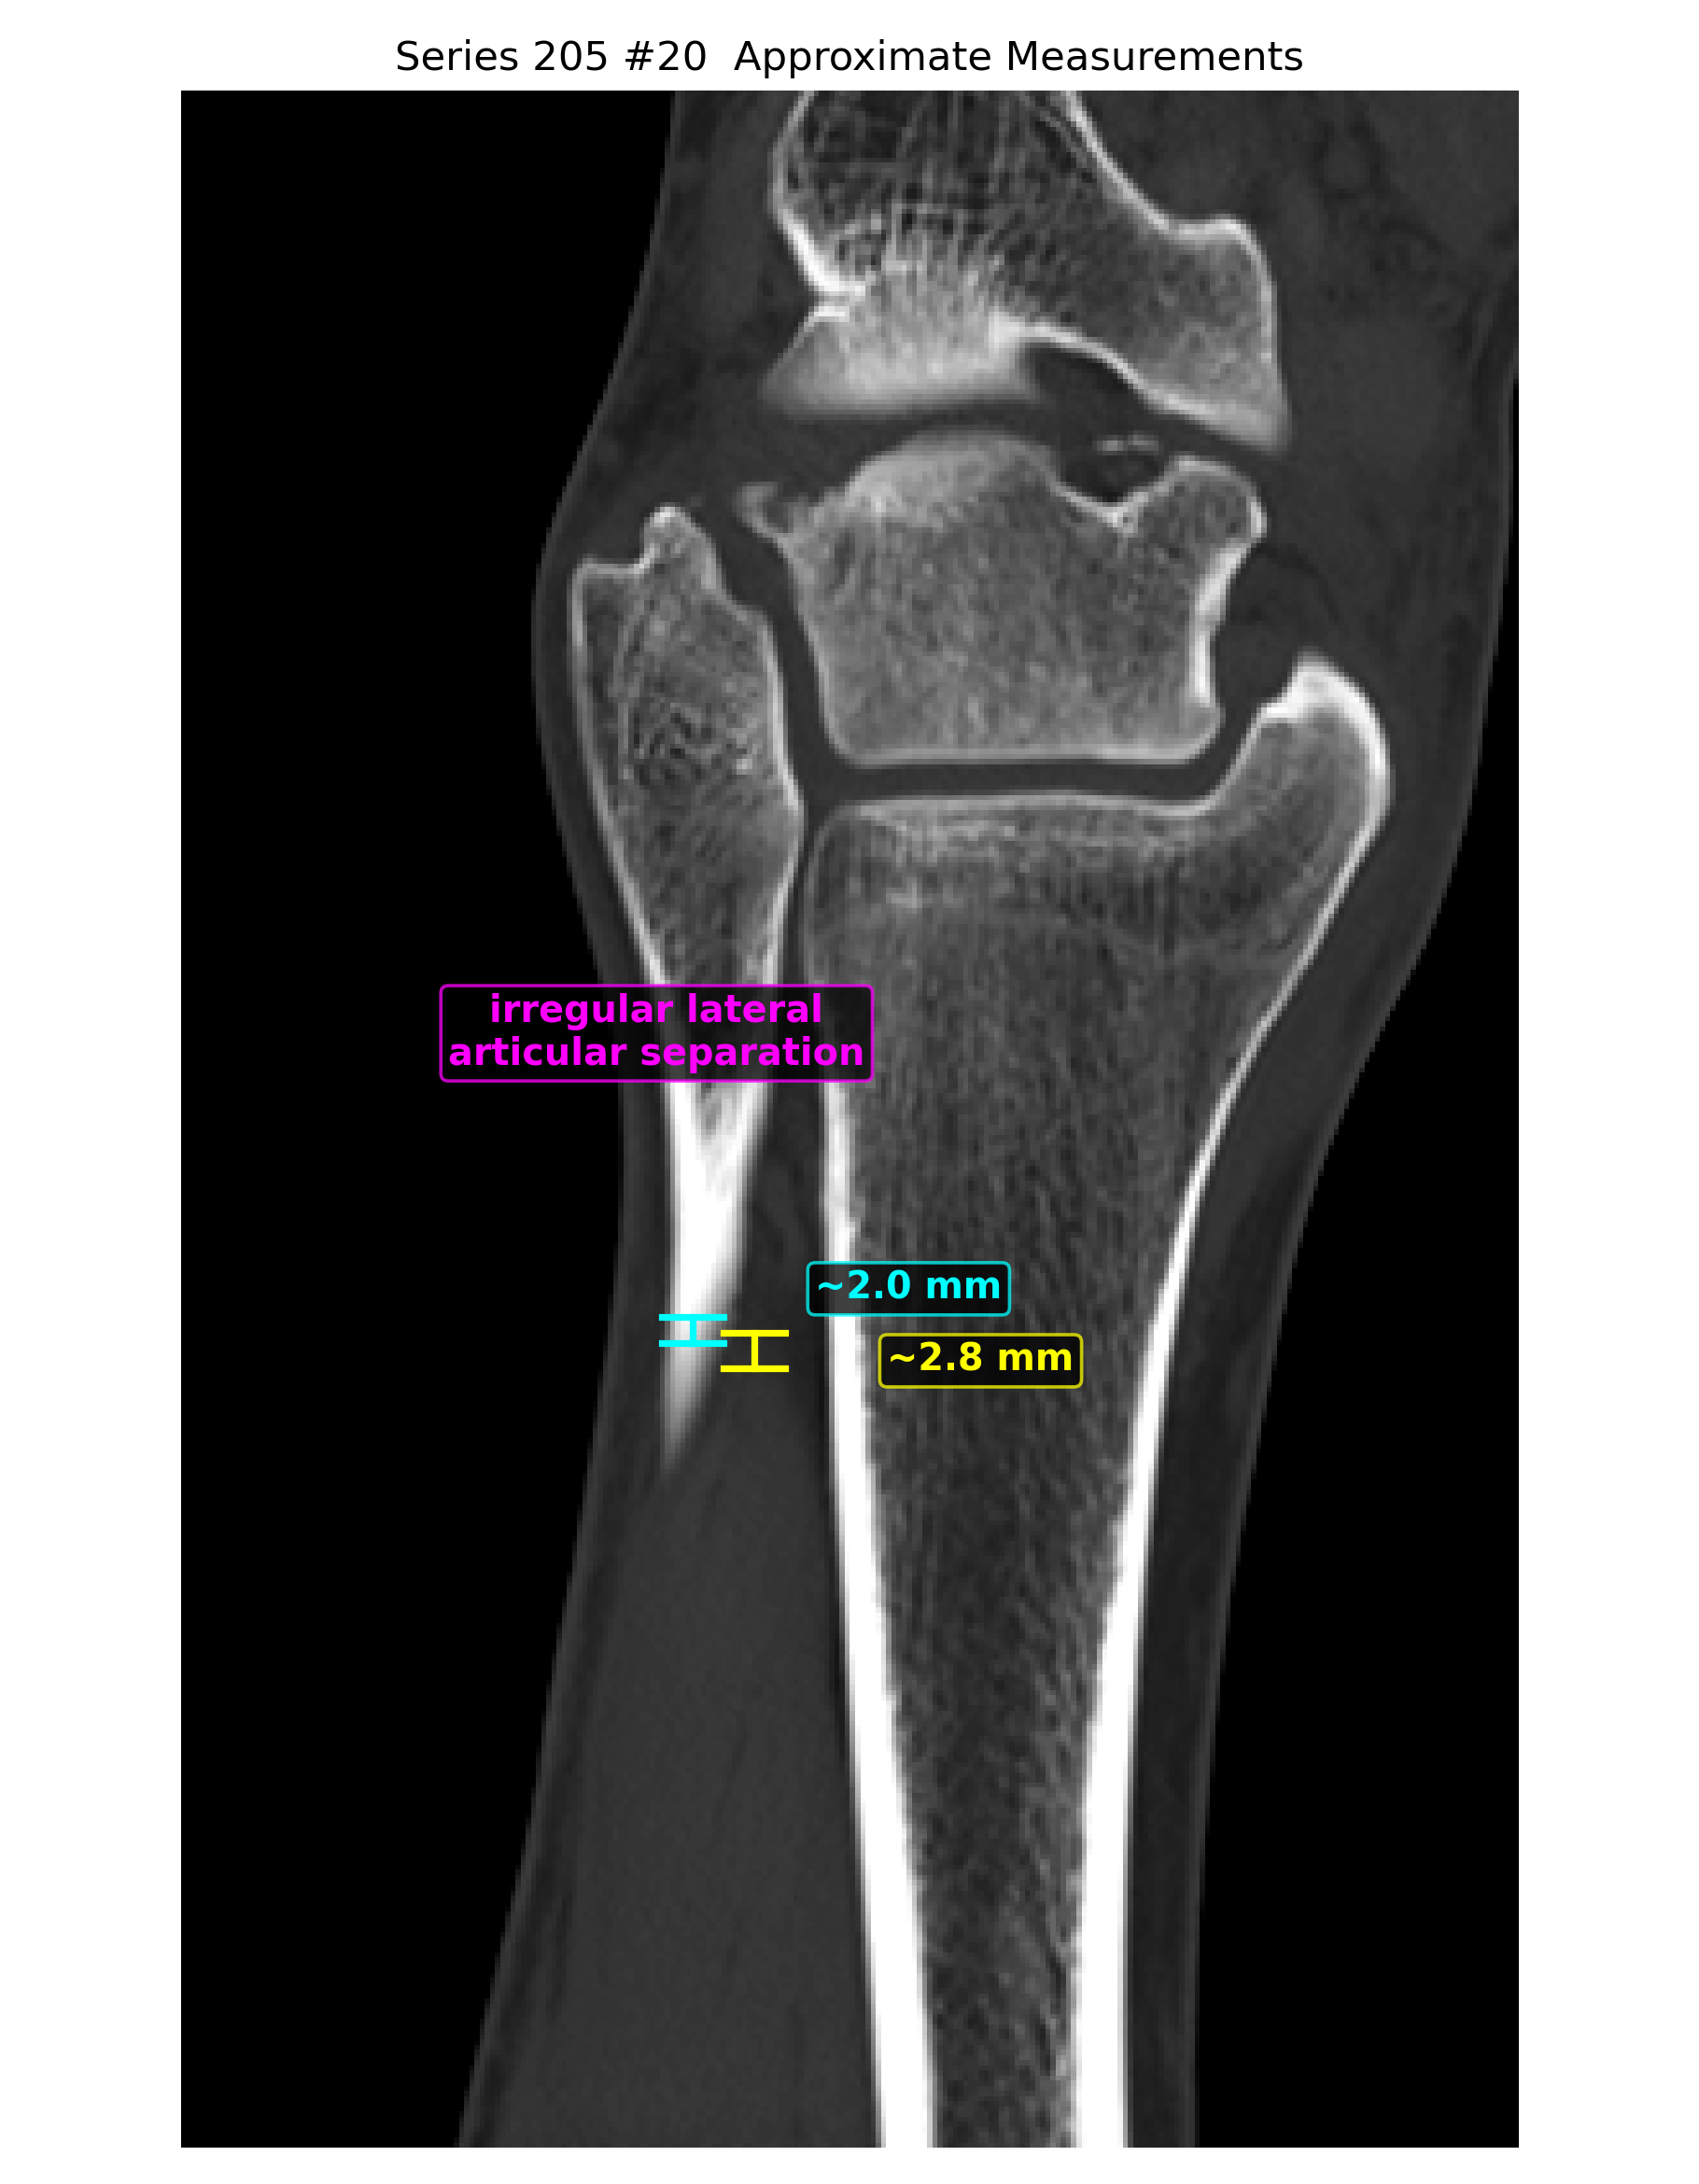

- 冠状位、矢状位和三维辅助重建里都能反复看到局部骨性不规则和分离感。

- 近似测量多次落在 2.0、2.3、2.8、3.3 mm 这个量级,支持轻度位移。

定量分析与标注图

以下毫米值为近似测量值,作用是帮助沟通位移量级,不等同于医生在工作站上的正式卡尺读数。

- 近似位移量级已经落在 2 到 3 mm 左右,值得认真评估手术阈值。